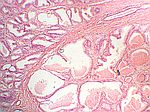

Prostatahyperplasie, HE